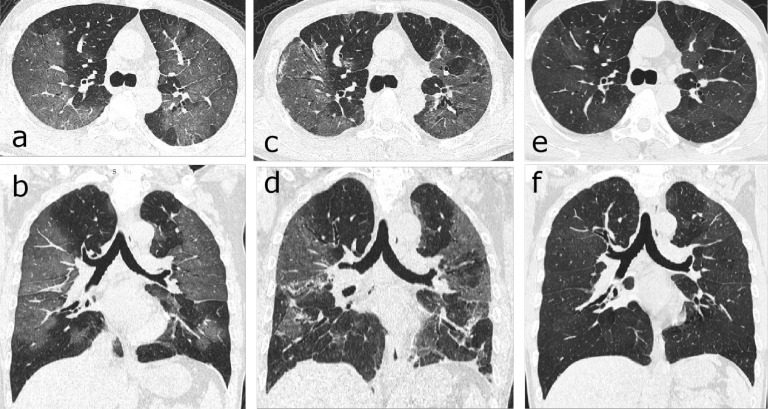

Figure 2:

Chest follow-up CT findings of COVID-19 pneumonia: (a) traction bronchiectasis; (b) parenchymal bands; (c) honeycombing; (d, e) thickening of the adjacent pleura.

Figure 3:

Serial CT scans of a 46-year-old woman with severe COVID-19 pneumonia. (a-c) The scan obtained on day 32 after symptom onset showed multiple ground-glass opacities (GGOs) and interstitial thickening with mild cylindrical traction bronchiectasis involving the middle lobe and lower lobe of the right lung. (d-f) The scan obtained on day 198 showed partial absorption of the abnormalities, reduced extension, traction bronchiectasis (thin arrows) and localized “honeycombing” (thick arrow) in the subpleural region of the right middle lobe.

Figure 4:

Serial CT scans of a 63-year-old man with emphysema and severe COVID-19 pneumonia. (a) The axial CT scan obtained on day 27 after onset of symptoms showed multiple ground-glass opacities (GGO) in the subpleural right lung. (b) The scan obtained on day 72 showed obvious absorption of the abnormalities. (c) The scan obtained on day 164 showed complete resolution.

Figure 5:

Serial CT scans of a 57-year-old man with severe COVID-19 pneumonia. (a, b) Axial and coronal thin-section CT scans obtained on day 9 after the onset of symptoms showed extensive ground-glass opacities (GGO) and interstitial thickening bilaterally. (c, d) Scans obtained on day 46 showed evolution to a mixed pattern of ground-glass opacities and consolidation with almost the same extent of lesions. (e, f) Scans obtained on day 159 showed a marked decrease in the density of GGO, with a slightly increased extension of the GGO (“tinted” sign or “melting sugar” sign, which defined as an imaging appearance of increased extension of the GGO or consolidation and decreased density).